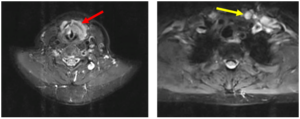

CASE LÂM SÀNG: CHẨN ĐOÁN BỆNH NHÂN ĐỒNG MẮC BA LOẠI UNG THƯ TẠI TRUNG TÂM Y HỌC HẠT NHÂN VÀ UNG BƯỚU, BỆNH VIỆN BẠCH MAI

CASE LÂM SÀNG: CHẨN ĐOÁN BỆNH NHÂN ĐỒNG MẮC BA LOẠI UNG THƯ TẠI TRUNG TÂM Y HỌC HẠT NHÂN VÀ UNG BƯỚU, BỆNH VIỆN BẠCH MAI GS. TS. Mai Trọng Khoa, PGS. TS. Phạm Cẩm Phương, PGS. TS. Phạm Văn Thái, BSNT. Đỗ Thị Thu Trang Trung tâm Y...